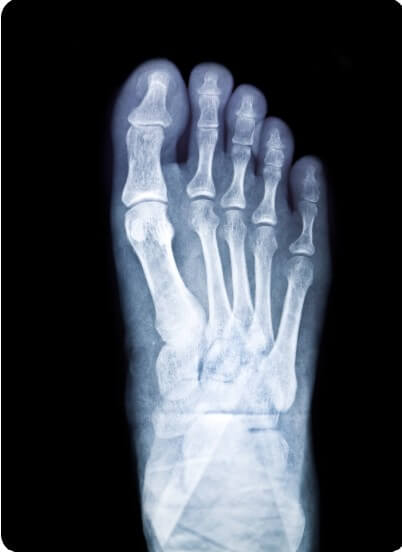

무지외반증 수술 종류 총정리

무지외반증은 단순한 미용 문제가 아닌, 걸을 때의 통증과 관절 기능 저하로 일상생활에 큰 불편을 주는 질환입니다. 다양한 수술 방법이 존재하며, 환자의 증상 정도, 뼈의 변형 각도, 나이, 활동 수준 등에 따라 적합한 수술법이 달라집니다. 이 글에서는 무지외반증 환자가 꼭 알아야 할 주요 수술법들을 구조적으로 정리해 설명합니다.

수술을 결정하기 전에는 정확한 진단과 영상 검사로 변형의 각도, 관절 안정성, 발의 구조적 특징을 파악해야 합니다. 무조건 절골술을 우선으로 보기보다, 환자의 나이, 활동성, 생활습관, 수술 후 기대 등을 고려해 가장 적합한 방법을 선택하는 것이 핵심입니다. 무지외반증은 환자 개인별로 매우 다양한 양상을 보이는 만큼, 족부 전문의와의 충분한 상담이 필요합니다.